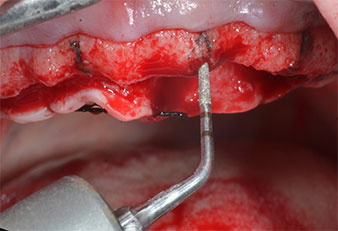

Ein flammenförmiges, diamantiertes piezochirurgisches Instrument (Piezomed I1) wurde verwendet, um die Implantatpositionen zu markieren und die Pilotpräparationen durchzuführen (Abb. 3). Dabei wurde darauf geachtet, eine Auf- und Abbewegung mit reduzierter Leistung, voller Spülung und niedrigem Druck (unter 300 g) anzuwenden. Als Nächstes wurde ein Pilotinstrument (Piezomed I2A/I2P) zur initialen Erweiterung der Implantatlager auf einen Durchmesser von 2 mm verwendet (Abb. 4), gefolgt von einem 3-mm-Instrument (Abb. 5).

Bei dichtem Knochen sollte das gesamte Set, einschließlich der Zwischeninstrumente Piezomed Z25P und Z35P verwendet werden, um die Osteotomien vor dem nächsten Schritt zu erweitern.

Diese Instrumente sind auch für die Aufbereitung bei interner Sinusbodenaugmentation in der Nähe der Sinusmembran indiziert oder wenn weniger als 4 mm Restknochenhöhe verbleibt.

Im vorliegenden Fall wurden die Instrumente Z25P und Z35P wegen des relativ weichen posterioren Knochens nicht verwendet, der problemlos mit dem I3A/I3P bearbeitet werden konnte.

Wegen des relativ harten Knochens (D2) an den Positionen 11 und 21 wurden die 10 mm langen Implantatlager in diesem Bereich abschließend mit einem 4-mm-Spiralbohrer, dem chirurgischen Winkelstück WS-75 L von W&H und dem W&H Implantmed Implantologiemotor in Verbindung mit dem optionalen W&H Osstell ISQ module präpariert. Im Gegensatz dazu wurde der weiche Knochen der Implantatlager im Seitenzahnbereich mit dem Piezomed I3P auf den abschließenden Durchmesser von 3 mm erweitert. Die Implantate wurden dann transgingival eingesetzt, die Einheildauer betrug drei Monate (Abb. 6-10). Die vorhandene Prothese wurde auf vier provisorischen Implantaten abgestützt (Abb. 8).